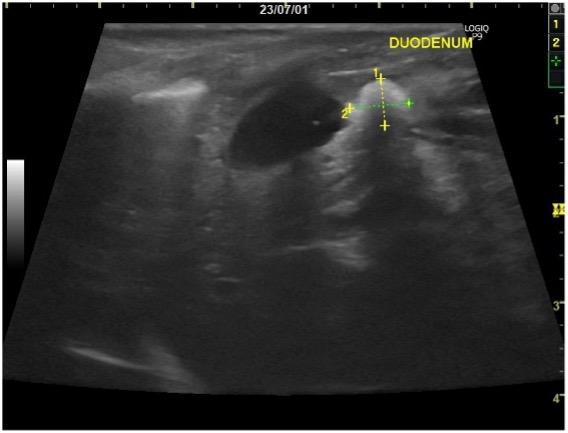

| 症状 | 3日前より食欲不振と嘔吐、下痢を主訴に来院されました。腹部触診にてお腹のなかにしこりが触知されました。エコー検査を行ったところ、左上腹部に腎臓腫瘍が認められました(図1)。オーナー様とご相談の上、摘出することにしました。 |

| 手術方法 | 全身麻酔下で開腹を行い、腎臓腫瘍の摘出を行いました(図2~3)。また、同時に膀胱内結石の摘出も行いました(図4)。 |